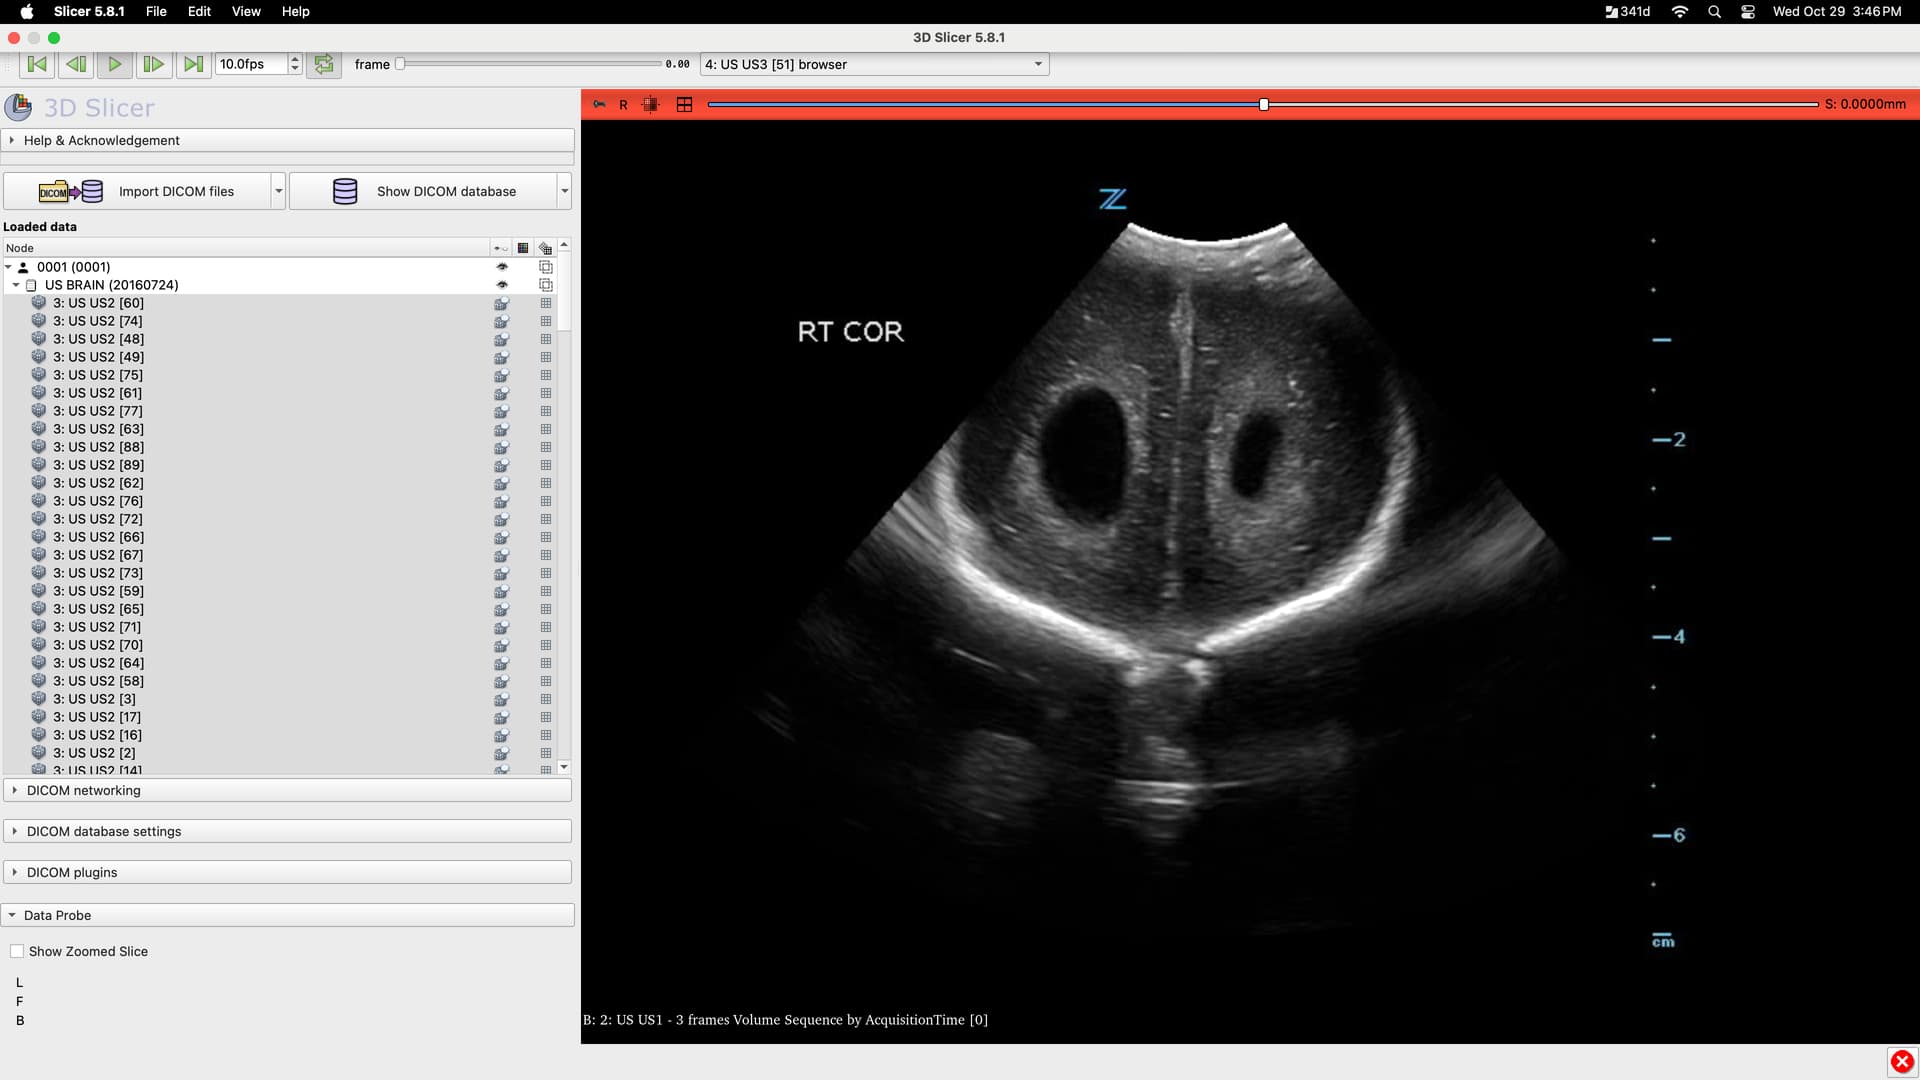

US segmentation, imaging browsing

I am trying to segment some ultrasound images. I imported the whole DICOM into Slicer but the images are out of order.

Is there a way to sort the images so they are in order and if so, is there a way to scroll through and look at all of them to select the best image (most applicable image) to segment for the project?